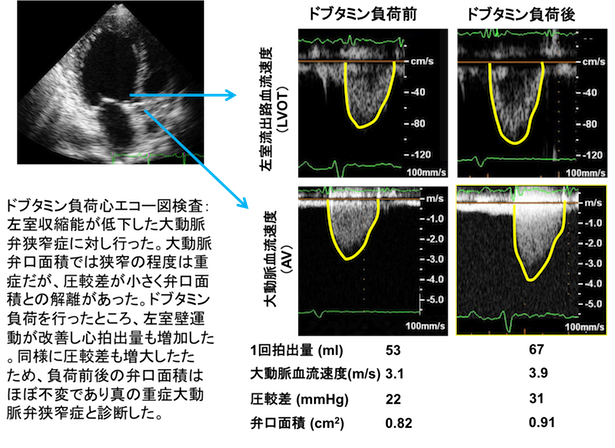

負荷心エコー図とは、何らかの負荷をかけることにより、安静時には認められなかった異常について心エコーを用いて検出する方法です。負荷の方法には運動負荷と薬物(ドブタミンやアデノシン)負荷とがあります。

虚血性心疾患、弁膜症、心筋症と対象となる疾患は様々です。虚血性心疾患については、運動やドブタミン負荷によって出現する心筋の壁運動の変化によって虚血の有無を評価します。

またアデノシン負荷前後の冠動脈血流速度を計測し冠動脈狭窄を推定します。さらに、安静時に既に虚血や梗塞によって心筋の壁運動低下を認める心筋については、ドブタミン負荷を行うことによって、心筋バイアビリティ(生存能)を評価することが出来ます。

薬物負荷心エコー図検査